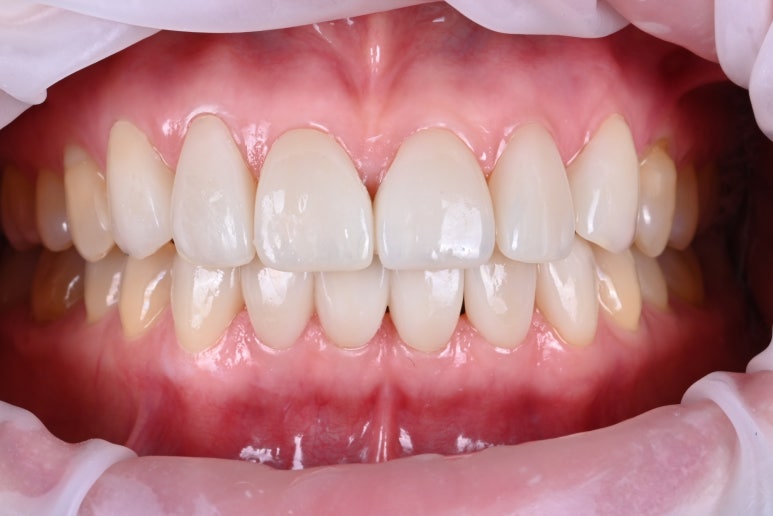

이번 환자분 같은 경우 위 앞니 6개, 아래 앞이 6개를 '레브네이트 엑스퍼트'로 치료하였습니다.

REVENATE EXPERT

정말로 치과의사도 전문가, 전담 세라미스트도 전문가의 손길이 느껴지도록 열심히 만들어보았습니다.

우선 색상이 개선되었습니다.

상당히 자연스러운 색상인듯 느껴지며, 잘~ 보시면 실제 치아와 유사하게 보일 수 있도록 치아의 목 부위, 몸통 부위, 끝 부위의 색을 살짝 살짝 조정해놓은 것을 보실 수 있을거에요.

그 다음으로 모양이 개선되었습니다.

좌우 대칭을 확보하였습니다. 조금 아쉽다면 위 앞니와 아래 앞니의 정중선이 약간 다른데, 치아를 최~대한 깎지 않다보니 위치까지 변경할 수 없기 때문이지요. 남들은 눈치못챌 포인트입니다.

앞니 벌어짐으로 생겼던 치아 사이 검은 공간이 사라졌습니다.

치아가 젊어지니 외모도 젊어집니다.

본연의 피부색과 어울리는 자연스러운 색상을 원하셔서, 오직 하얀 색깔만을 추구하는 것이 아닌 마치 젊었을 때의 치아 색상같은 모습으로 만들어드려보았습니다!

레브네이트 엑스퍼트는 이렇게 앞니 벌어짐, 잇몸사이 공간을 채워드리고, 치아의 수직 수평을 맞춰 안티 에이징의 효과까지 가져오는! 그런 멋진 작품이랍니다.